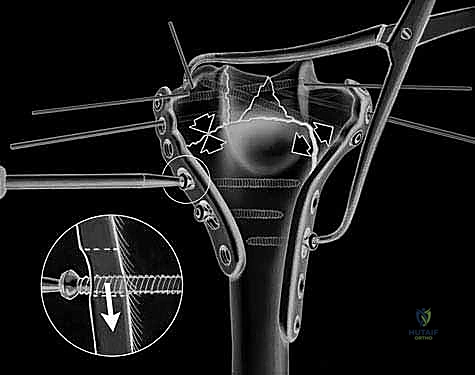

The fracture reduction sequence follows a strict "inside-out" and "bottom-up" philosophy. The primary objective is the anatomical restoration of the articular block (the "tie"). The trochlear and capitellar fragments are meticulously debrided of hematoma, reduced using pointed reduction forceps, and provisionally stabilized with smooth Kirschner wires. This articular assembly is then definitively fixed using headless compression screws or countersunk cortical lag screws, ensuring no hardware violates the joint surface. Once the articular block is reconstituted into a single, solid unit, it is reduced to the medial and lateral columns of the humeral diaphysis. Provisional fixation to the shaft is achieved with K-wires, and orthogonal fluoroscopy is utilized to confirm anatomical alignment, particularly the crucial 30-degree anterior tilt of the articular surface.

Definitive osteosynthesis is achieved through the application of dual pre-contoured anatomical plates. Following the principles of parallel plating, a plate is applied to the medial ridge and another to the lateral ridge of the distal humerus. The plates are positioned to maximize screw purchase in the distal articular block; ideally, multiple screws should interdigitate through the articular fragments, creating a "rebar" effect. The plates must be compressed to the bone using standard lag techniques or articulated tension devices before deploying locking screws. The stability of the construct is then rigorously tested by taking the elbow through a full, unhindered range of motion. Finally, the olecranon osteotomy is meticulously repaired using the previously drilled lag screw supplemented with a figure-of-eight tension band wire, or via a dedicated proximal ulna locking plate, ensuring rigid fixation to allow for immediate postoperative rehabilitation.